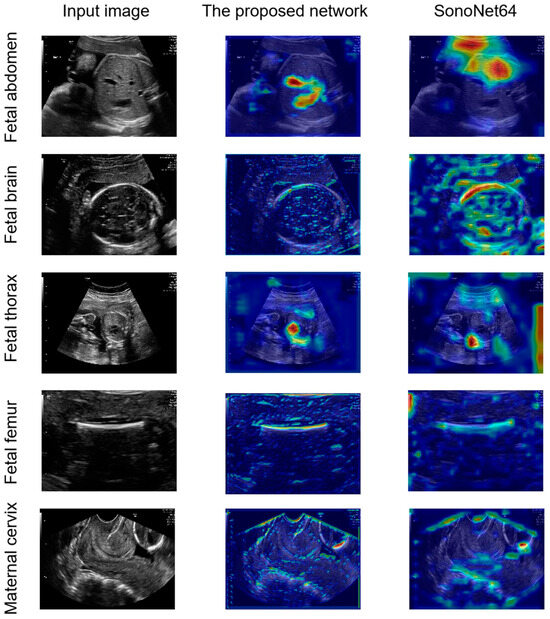

The open-access dataset used in this paper was made public in 2020 by Burgos-Artizzu et al. [22]. The 12,400 images in the dataset were manually labeled by an expert maternal fetal clinician and divided into 6 categories: fetal abdominal standard plane (Figure 1a), fetal brain standard plane (Figure 1b), fetal femur standard plane (Figure 1c), fetal thorax standard plane (Figure 1d), maternal cervix (Figure 1e), and other (Figure 1f). The fetal brain standard plane was further categorized into fetal trans-ventricular standard plane (Figure 1(b-1)), fetal trans-thalamic standard plane (Figure 1(b-2)), fetal trans-cerebellum standard plane (Figure 1(b-3)), and other brain standard plane (Figure 1(b-4)). The dataset was randomly divided into training, validation, and testing sets in a ratio of 8:1:1, resulting in 9916 images for training, 1243 for validation, and 1241 for testing. The specific number of images used for classifying six and nine categories is outlined in Table 1 and Table 2.

Figure 1. Representative images from Burgos-Artizzu’s dataset [22] depicting various fetal ultrasound standard planes: (a) fetal abdominal standard plane; (b) fetal brain standard plane; (b-1) fetal trans-ventricular standard plane; (b-2) fetal trans-thalamic standard plane; (b-3) fetal trans-cerebellum standard plane; (b-4) other brain standard plane; (c) fetal femur standard plane; (d) fetal thorax standard plane; (e) maternal cervix; and (f) other. (af) are samples for six categories classification. (af) are samples for nine categories classification.